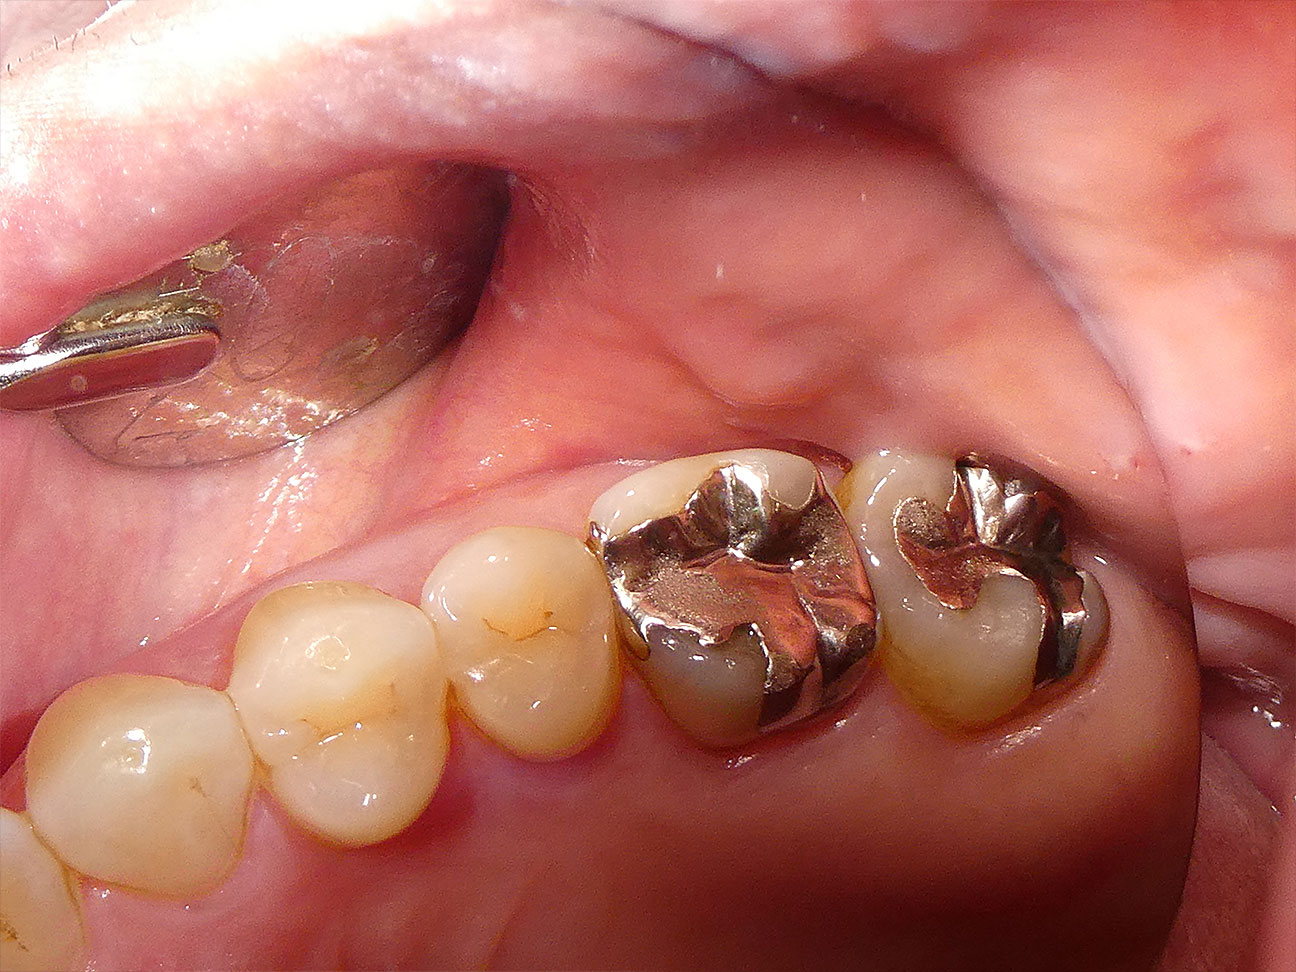

STEP1 ご来院時

奥歯を保険の金属の詰めもの(パラジウムアンレー)で治療されていましたが、保険の金属による詰めものは長く使うあいだにすき間が生まれ、そのすき間から虫歯菌が入ることで、どんなに丁寧な歯磨きを頑張っても金属の詰めものの下では虫歯が進行していきます。写真を目視されても段差や隙間はお分かりになると思います。